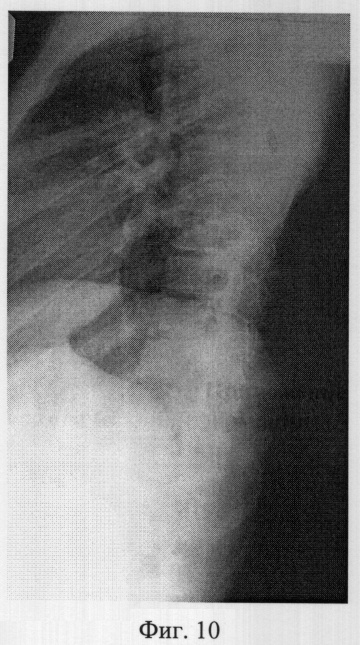

Фиг.10 – рентгенограмма в боковой проекции сколиотически измененного позвоночника больной X. до операции (грудная локализация);

Пример 3. Больная X., 11 лет, 08.07.05 поступила в отдел новых технологий в вертебрологии и нейрохирургии СарНИИТО по поводу диспластического прогрессирующего нестабильного правостороннего грудопоясничного сколиоза III степени.

В СарНИИТО ей были выполнена рентгенография в стандартных проекциях: фасная (фиг.9) и боковая (фиг.10) рентгенограммы.

По фасной рентгенограмме определены следующие показатели позвоночника:

– угол сколиотической деформации по Кобб: стоя – 50°, лежа – 48°;

– индекс стабильности по Казьмину – 0,82;

– определена протяженность дуги в 7 позвонков (от Th3 до Тh11),

– определена вершина деформации – Th6.

По рентгенограммам проведена оценка зрелости позвоночника: тест Риссера составил R-1, кольцевые апофизы тел позвонков четко определены у тел Th4-Th9, Тh10 по дуге искривления, что свидетельствует о высокой потенции роста больной и прогрессировании деформации.

Поэтому выполнение оперативного вмешательства из заднего доступа в полном объеме невозможно. Выполнение заднего спондилодеза при протяженности деформации в 7 позвонков (Th3-Th11) в сочетании с высоким потенциалом роста и открытыми пластинками роста позвонков может привести в последующем к формированию тяжелой деформации позвоночника по типу синдром «коленчатого вала».

Заключение: при протяженности сколиотической дуги в 7 позвонков с вершиной деформации в пределах одного грудного отдела позволяет провести вентральную коррекцию центрального угла деформации и фиксацию металлоконструкцией из переднего доступа.